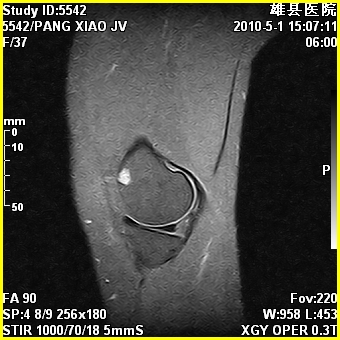

标题: MRI2894:患者右膝关节疼痛两月余,无明显外伤史 [打印本页]

标题: MRI2894:患者右膝关节疼痛两月余,无明显外伤史

右股骨下端前内侧类圆形异常信号,位于干骺端,呈长t1长t2改变,但信号不均,t1图上病灶中心见小片状稍高信号影,t2图上见散在稍低信号影,stir像呈高信号,因病灶较小,缺乏特征性改变,结合患者年龄及部位,考虑嗜酸性肉芽肿可能性大。胫骨关节面下的小囊状异常信号,如果一元论考虑则为嗜酸性肉芽肿,不过发生在这个部位的少见,二元论考虑为邻关节骨囊肿。半月板与前后交叉韧带均未见异常。

内生软骨瘤

年龄略大 内生软骨瘤?

骨样骨瘤?内生软骨瘤?